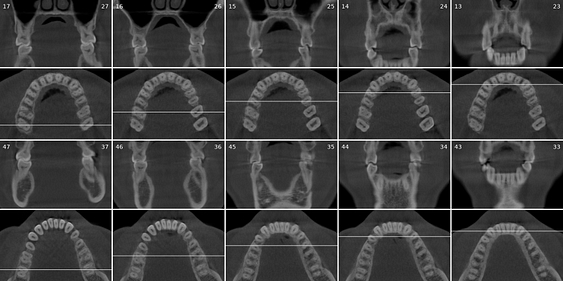

Diagnocat offers radiological reports for intraoral X-rays (PBWs and PAs), OPG, and CBCT. Your trusty advisor, in a way.

Every tooth in the radiograph is identified by its ISO (FDI) or Universal (American) number automatically. It can even pick up missing teeth. This is all labeled and identified in its intelligent reporting system.

A report is generated and outlines the health of every single tooth. For each tooth, Diagnocat can identify 25 different possible findings for 2D images and more than 65 for 3D radiographs. Each tooth report can be approved, and the dentist’s signature can be added to the overall report, which adds accountability to the report's contents.

Generating a report using Diagnocat for a full mouth series of up to 24 2D radiographs (PAs, PBWs) takes less than a minute. Yes, it is impressively fast.

Generating a full report of a full-mouth CBCT 3D radiograph takes four to six minutes. We are talking about going over every slice with a fine-tooth comb. This has huge benefits, as a maxillofacial radiologist may take up to 40 minutes to fully report on a 3D CBCT radiograph.